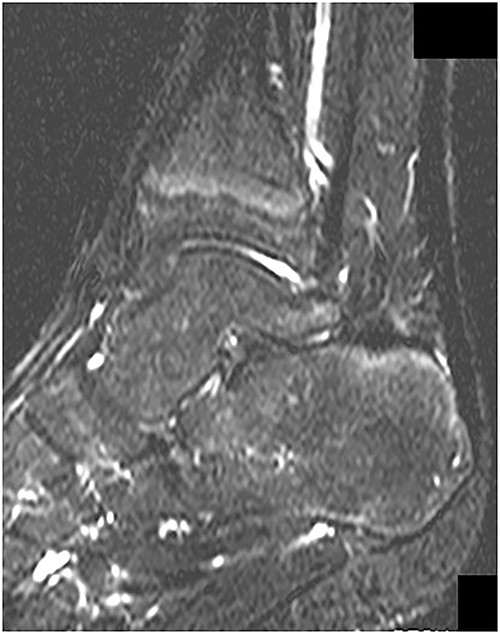

Postoperatively, intravenous antibiotic therapy using cefazolin (6000 mg per day) was continued for 10 days until laboratory results was within normal. A non-weightbearing splint was applied for postoperative 1 week. Active range of motion exercises and partial-weightbearing were started at 1 week postoperatively, and full-weightbearing at 2 weeks postoperatively. At 4 weeks after the surgery, he could return to the original sport at preinjury level without symptoms and complications. In addition, MRI revealed no abnormal signs at 1 year postoperatively (Fig. 5). Two years after the surgery, he remained a competitive soccer player without symptoms and recurrence.

MRI revealed no abnormal signs on short TI inversion recovery images at 1 year postoperatively.